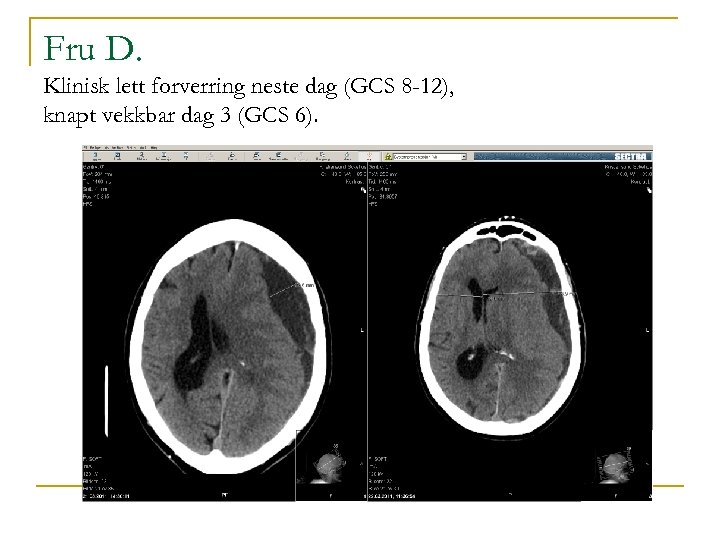

Fru D. , forts. n n Innlegges pga akutt funksjonssvikt, konfusjon. Dårligere gangfunksjon, desorientert, litt trøtt. Hadde falt 2 – 3 uker tidligere. Ingen sikre fokalnevrologiske utfall ved innkomst. GCS 14. BT 179/79. CT viser kronisk subduralt hematom frontotemporoparietalt venstre side, og ca 15 mm midtlinjeforskyvning. Avtaler operasjon om ca 3 dager, nuller ut Albyl og Persantin så lenge.

Fru D. Klinisk lett forverring neste dag (GCS 8 -12), knapt vekkbar dag 3 (GCS 6).